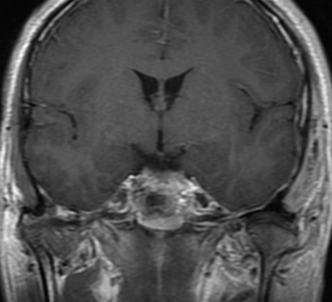

术前影像

入院后行术前检查,核磁共振显示:斜坡偏左占位,脑膜瘤可能性大。

左侧斜坡脑膜瘤